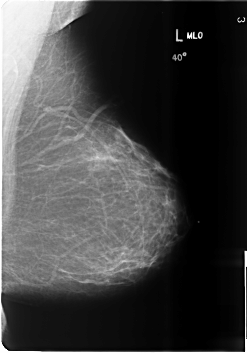

B_3486_1.LEFT_MLO

B_3486_1.LEFT_CC

LEFT_CC LINES 6016 PIXELS_PER_LINE 4128 BITS_PER_PIXEL 12 RESOLUTION 50 NON_OVERLAY

LEFT_MLO LINES 6000 PIXELS_PER_LINE 4184 BITS_PER_PIXEL 12 RESOLUTION 50 NON_OVERLAY